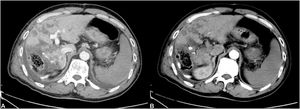

In this study, the use of postoperative anticoagulants was an independent risk factor for liver failure. Postoperative anticoagulants can greatly reduce the occurrence of liver failure. Circulatory failure during PHLF is similar to circulatory failure with sepsis [23]. The commonly observed pathophysiological changes include enhanced vascular permeability, diffuse endovascular coagulation, and peripheral vasodilatation, which are represented clinically by reduced peripheral resistance and hemodynamic instability [24]. We found many of the PHLF patients had typical CT images of PHLF, including portal vein thrombosis and obstruction, as well as large infarcts in the liver (Fig. 6). Studies have shown that postoperative hypercoagulability is caused by liver coagulation dysfunction [25]. We speculate that liver failure may be the process of liver disseminated intravascular coagulation (DIC) leading to liver infarction. Liver DIC is a complex pathological process triggered by specific events. Pathogenic factors activate the coagulation system, causing activation of platelets and deposition of fibrin, leading to DIC. These patients had prominent clinical manifestations similar to hepatic vascular embolism and microcirculation dysfunction. Liver infarction refers to partial hepatic avascular necrosis caused by severe stenosis or complete occlusion of a branch of the hepatic artery or portal vein. The Pringle maneuver, use of hemostatics, and lack of anticoagulant usage can lead to thrombosis, which aggravates stenosis or occlusion. Hemostasis is an integral and very important aspect of surgical practice [26]. Our medical team uses the following additional strategies to prevent PHLF: use of anti-infection medications, hormone therapy, intestinal probiotics, postoperative anticoagulants, and terlipressin (which plays a role in improving blood flow). Further studies on the benefits of such strategies on pathology and molecular biology are needed. We found it impossible to perform CT imaging on all the PHLF patients for the following reasons: (i) the rapid onset of PHLF; (ii) severity of illness making patients unable to be safely scanned; and (iii) in some cases, the rapid demise of the patient. Therefore in the absence of complete data, we did not include the presence of portal vein thrombosis on CT images as a statistical variable. However, in future, we plan to further explore the diagnostic and predictive value of CT imaging for portal vein thrombosis in PHLF. In terms of the standard of postoperative anticoagulant usage, we took the increase in DD-dimer level as the anticoagulant index. Some studies have shown that the earlier the anticoagulant is started, the higher the recanalization rate [27]. Postoperative anticoagulants were used in patients who demonstrated no obvious bleeding events, and in this study we performed hemostatic and small-scale resections. In this study, the patients who used anticoagulant drugs after the operation did not show an increased bleeding rate.